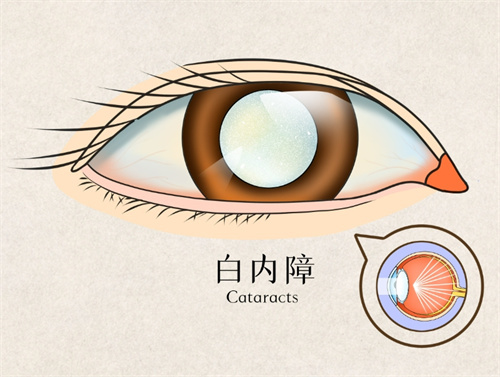

核心优势:民众眼科以“全术式解决方案”著称,其手术室配备Alis眼内激光机、YAG激光等设备,可同步开展青光眼、白内障、眼底病联合手术。

青光眼白内障联合手术:一次手术解决两种眼病,减少患者反复麻醉风险,术后视力修复周期缩短。